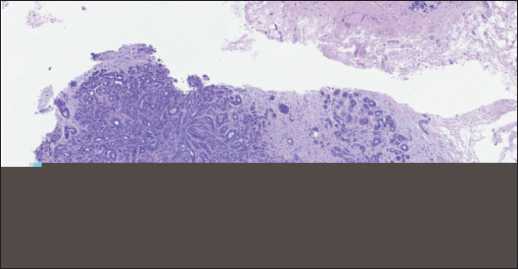

По данным патологоанатомического исследования трепан-биоптата опухоли определялись фрагменты молочной железы с нарушенной архитектоникой за счёт разрастания опухоли, состоящей из плотно расположенных клеток с округлыми и овальными гиперхромными ядрами и скудной цитоплазмой, окруженными гиперпластическими миоэпителиальными клетками. Митотическая активность не определяется. Опухолевые клетки формируют трабекулярные и тубулярные структуры. Строма опухоли умеренно выражена, с очаговым гиалинозом. Заключение: морфологи- ческая картина соответствует аденомиоэпителиоме молочной железы (рис. 4).

Рис. 4. Микрофото. Аденомиоэпителиома молочной железы, ×20. Примечание: рисунок выполнен авторами Fig. 4. Microphoto. Breast adenomyoepithelioma, ×20.

Note: created by the authors